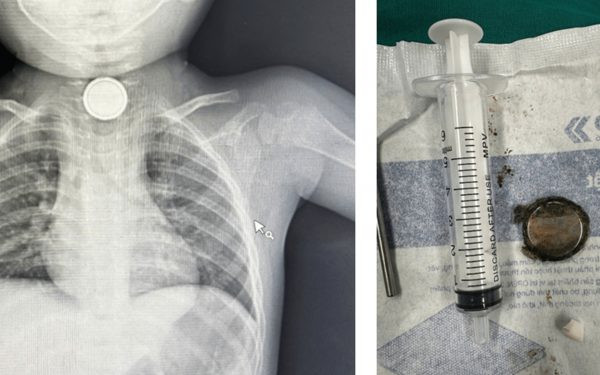

Tại đây, các bác sĩ thăm khám, làm xét nghiệm máu, chụp Xquang phổi và siêu âm ngực bụng, Kết quả Xquang cho thấy có dị vật hình tròn phần trên của ngực trẻ nên được hội chẩn các bác sĩ chuyên khoa tai mũi họng, tiêu hóa nội soi, sau đó gắp ra được cục pin tròn dẹp đường kính 1,1cm nằm ở 1/3 trên thực quản.

Ghi nhận cục pin rỉ sét và viêm loét hoại tử niêm mạc thực quản. Các bác sĩ đã đặt một ống thông mũi – dạ dày để giữ cho thực quản không bị chít hẹp. Trẻ được dùng kháng sinh, phổ rộng, kháng viêm, thuốc bang niêm mạc đường tiêu hóa, thuốc giảm tiết dịch đường tiêu hóa.

| Phim chụp và viên pin sau khi được lấy ra ngoài. Ảnh: BVCC |